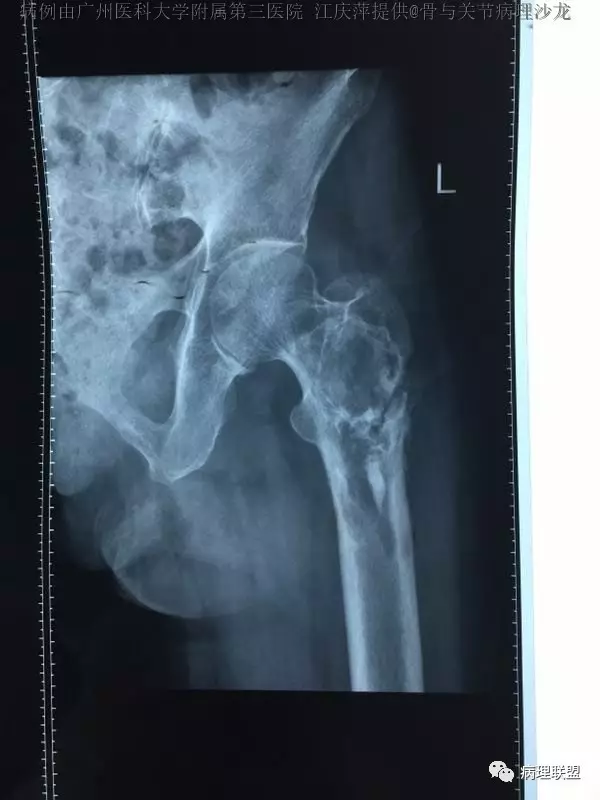

女,63,反复髋关节疼痛30年,活动受限2周(病例由广州医科大学附属第三医院 江庆萍提供,致谢)